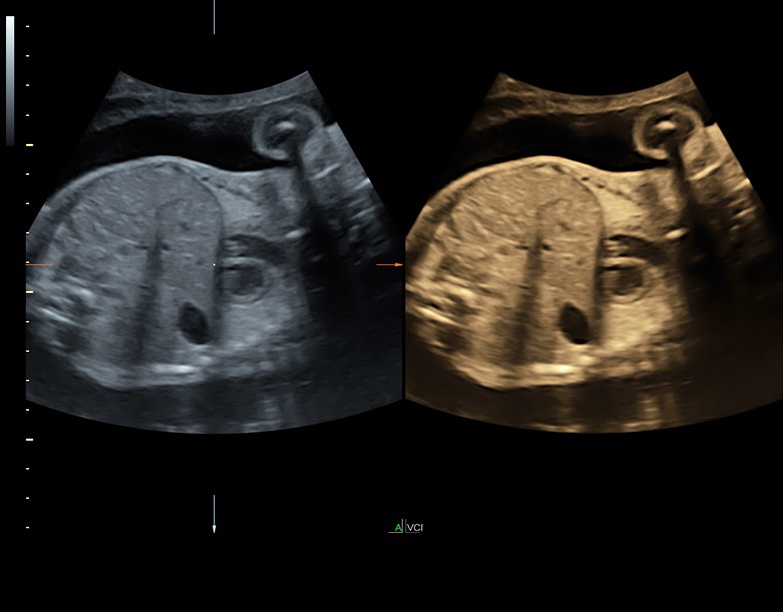

Ультразвуковая платформа Voluson S8 представляет собой оборудование экспертного класса с передовыми возможностями и высоким уровнем автоматизации процессов. Она позволяет проводить сканирование в режимах 2D, 3D и 4D с высоким качеством изображений.

Аппарат Voluson S8 базируется на надежной платформе VCA, которая имеет множество положительных отзывов. Она обладает высококонтрастной технологией объемной реконструкции, обеспечивая качественное воспроизведение изображений. Информация выводится на широкоформатный цветной монитор размером 23 дюйма для убедительной демонстрации плода будущим родителям и облегчения работы врача.

• Высокое качество изображений: Voluson S8 обеспечивает высококачественные изображения, позволяющие детально оценить состояние плода и обнаружить возможные патологии.

• Технология SonoRenderlive: Эта технология облегчает получение 3D/4D изображений путем автоматического изменения положения плоскости визуализации в зависимости от движений плода. Она позволяет получить реалистичные и объемные изображения, что полезно для демонстрации плода будущим родителям и для дополнительного анализа.